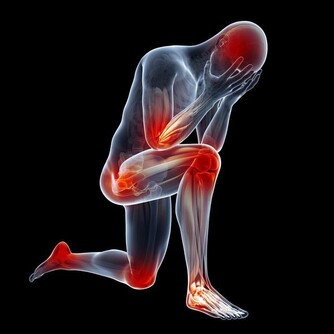

中醫中,十二個時辰代表人體十二個臟腑。如果在對應的時辰裡相關的臟腑出現問題,最好的緩解改善方法就是疏通經絡。